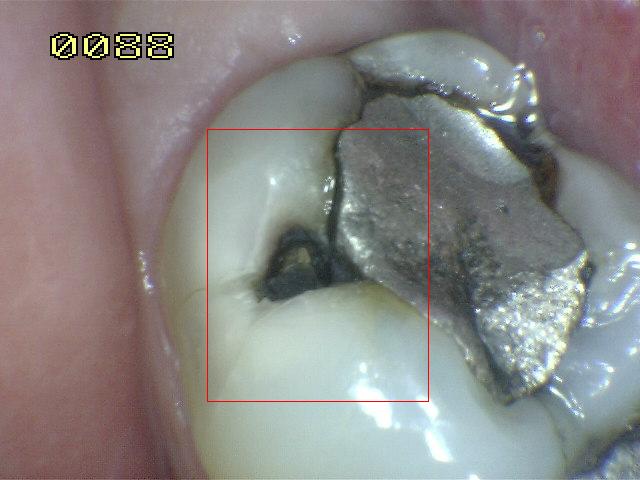

Sistema Internacional para la Detección y Evaluación de Caries (ICDAS)

¿Determine los códigos pertinentes a cada imagen?

Click en el hipervínculo: Para comparar el resultado de su diagnóstico